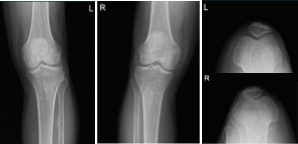

He presented X Ray of his bilateral knees, lumbar spine, and right hand from Zwanger. His Xray results showed mild osteoarthritic degenerative changes. There are no fractures. For his lumbar spine mild multilevel lumbar degenerative changes. For his right hand, normal right hand.

Left and Right knee X-ray complete with patella